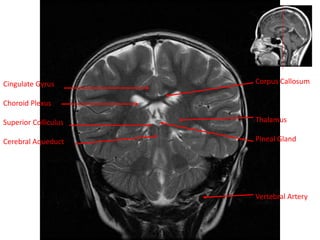

Cingulate Gyrus

Choroid Plexus

Superior Colliculus

Cerebral Aqueduct

Corpus Callosum

Thalamus

Pineal Gland

Vertebral Artery

Cingulate Gyrus Choroid Plexus SuperiorColliculus Cerebral Aqueduct Corpus Callosum Thalamus Pineal Gland Vertebral Artery